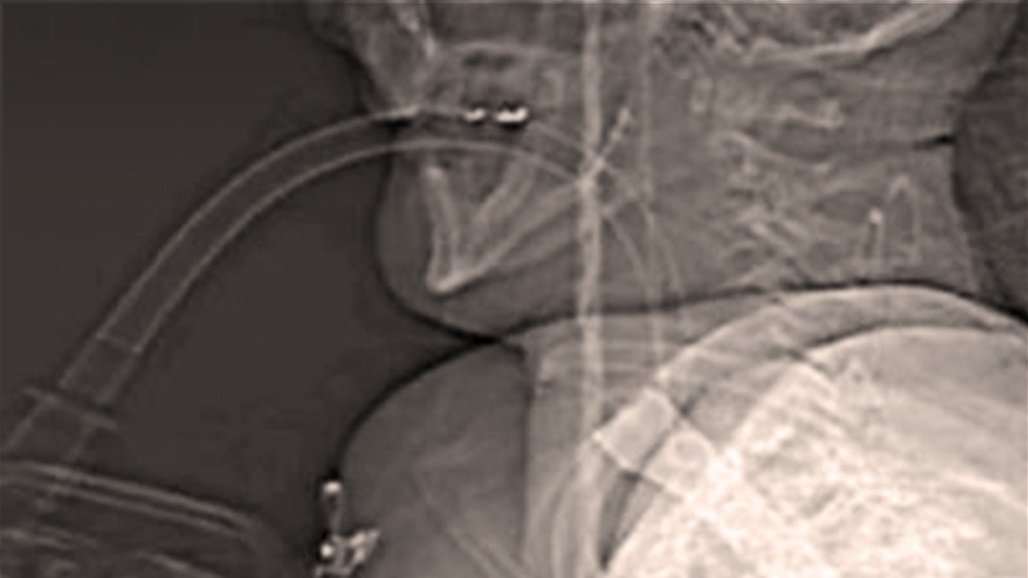

الأشعة السينية تبيّن استقرار سكين في حلق رجل بعد مشاجرة.

أظهرت الأشعة السينية خنجرًا يبلغ طوله 14 سنتمترًا استقرّ في حلق رجل بعدما طُعن به أثناء مشاجرة في شيلدون الواقعة في مقاطعة دورهام في إنجلترا.

ورغم أن الرجل نجا بأعجوبة، بعد خضوعه لعملية جراحية اتخذت ساعات لإزالة الخنجر بعد أن تركه على بعد ملليمترات فقط من الموت، إلّا أنه سيتحملّ نتائج إصابته طوال حياته.

وأكّد المحقّقون أنه محظوظ بالبقاء على قيد الحياة وأوضحوا أن شابًّا عمره 28 عامًا طعن هذا الرجل بسكين مطبخ، ما استدعى الحكم عليه بالسجن لسبعة أعوام وشهرين.